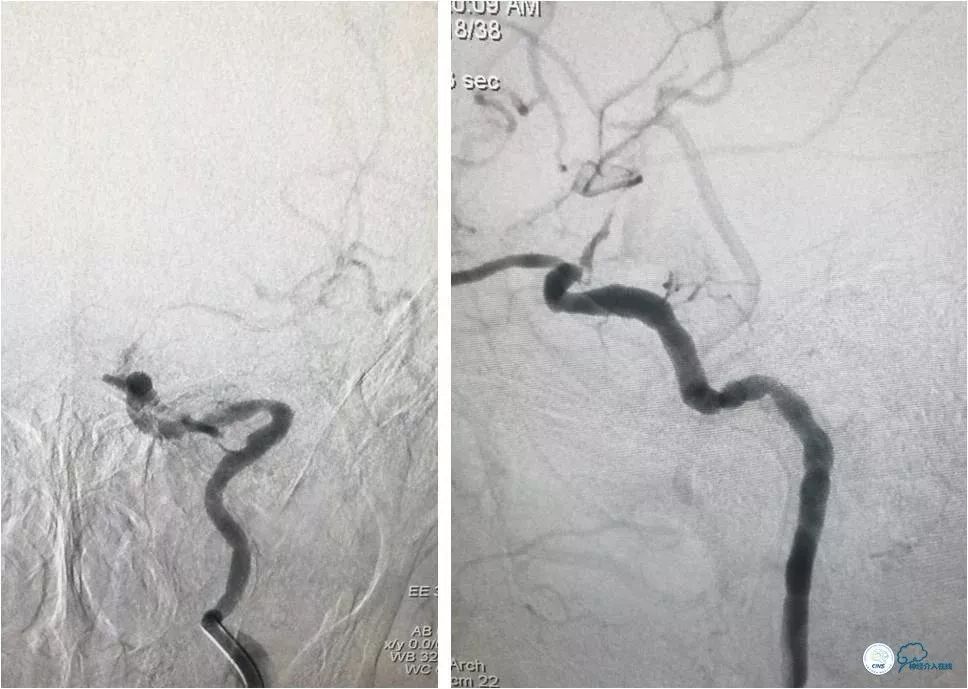

更换为Pilot-50微导丝(0.014″,200cm),越过狭窄起始段,再次更换为Synchro微导丝,送至左大脑中动脉M2段(图9)。

图9

跟进Echelon 10微导管以期通过病变未获成功,遂逐节剪断微导管撤出微导管,保留微导丝。送入Ultra-soft球囊(2.0mm×20mm)至狭窄段近端及远端行球扩后造影显示狭窄程度和前向血流均有所改善(图10)。

图10